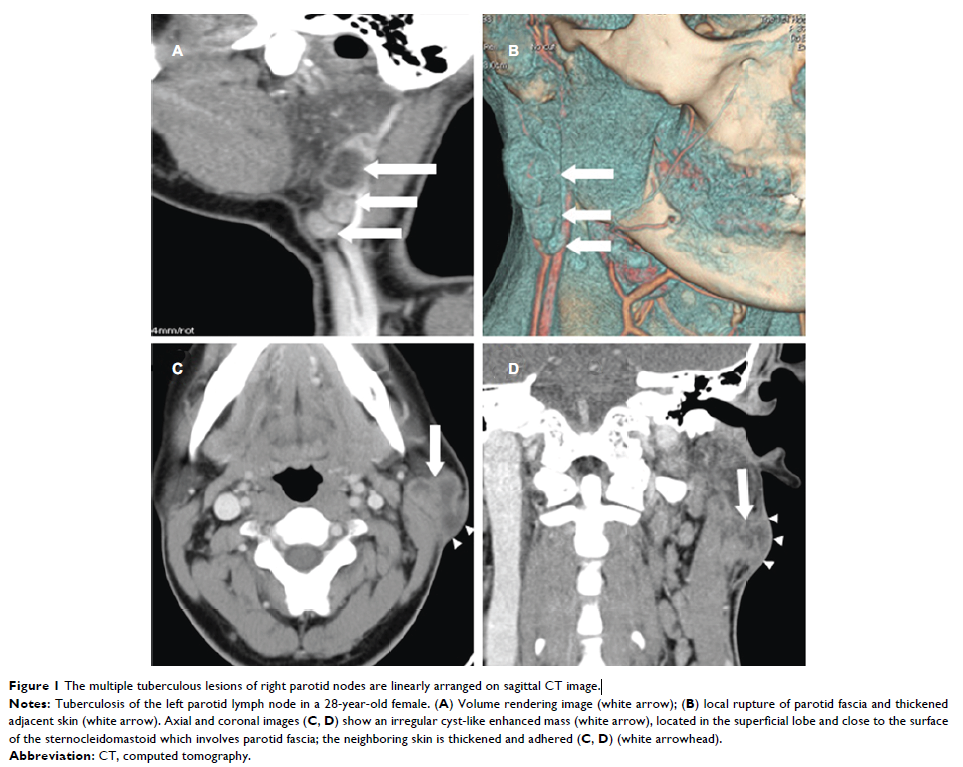

Original Research

- 作者:Dan Zhang, Xiaojiao Li, Hua Xiong, Chao Yang, Fajin Lv, Xianlong Huang, Qi Li, Zhuoyue Tang, Tianyou Luo

- 期刊:Infection and Drug Resistance